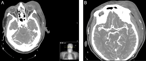

Primitive synovial sarcoma of suboccipital region in child

Ploutarchos Karydakis and others

Journal of Surgical Case Reports, Volume 2018, Issue 10, October 2018, rjy286, https://doi.org/10.1093/jscr/rjy286